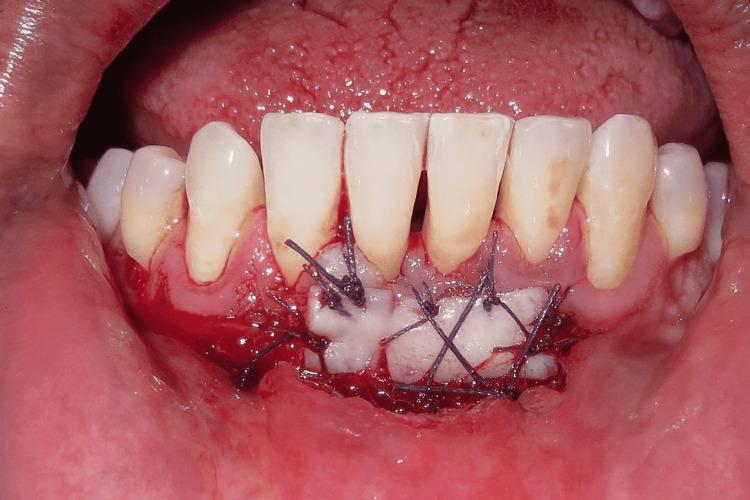

This case report describes Clark's technique of vestibuloplasty to treat shallow vestibule and, in addition, the use of free gingival autograft to augment attached gingiva to treat Miller's recession. Vestibuloplasty is performed to deepen a shallow vestibule. Different vestibuloplasty techniques are used to deepen the shallow vestibule by modifying the soft tissue attachment. A 29-year-old male presented to the Department of Periodontics and Oral Implantology, Regional Dental College, Guwahati, India with the chief complaint of bleeding from the lower anterior along with the gingival recession. Maintenance of regular oral hygiene was an added hindrance. The combined technique of vestibuloplasty and use of free gingival graft was performed to achieve dual benefits of increasing the vestibular depth and attainment of a thick gingival phenotype.

本病例报告描述了克拉克前庭成形术治疗浅前庭的技术,此外,还介绍了使用游离龈自体移植术增加附着龈以治疗米勒氏牙龈退缩的方法。前庭成形术用于加深浅前庭。通过改变软组织附着来加深浅前庭,采用了不同的前庭成形术技术。一名29岁男性因下前牙出血伴牙龈退缩,前往印度古瓦哈蒂地区牙科学院牙周病与口腔种植科就诊。保持规律的口腔卫生是一个额外的障碍。采用前庭成形术和游离龈移植术相结合的技术,以实现增加前庭深度和获得厚龈表型的双重益处。